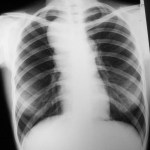

Hodgkin’s Disease

This 19 year-old female patient presented with general malaise. A chest x-ray demonstrates lobulated mediastinal widening, most...